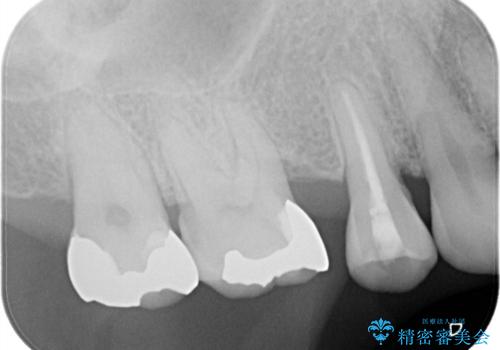

- 以前詰めた、インレーが外れたことを主訴に来院されました。

隣の歯にも虫歯を認めたためまとめて治療を行いました。

辺縁隆線にクラックラインを認め、破折防止のためにクラウンによる治療を希望されました。